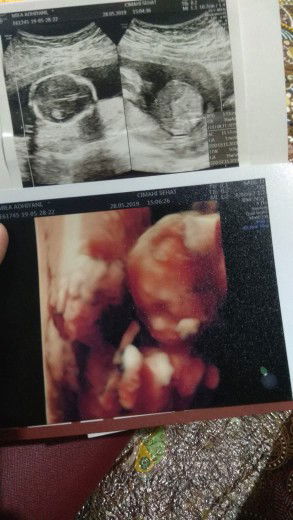

USG

Selamat pagi bunda... Mau tanya niiih,kira2 klo di USG biar kelihatan janin nya di usia kandungan k brpa bulan ya bun ? Tks ??

Sya tiap bulan usg 2D aja lumayan jelas kok anggota2 badan nya , kyk jari , tangan dan kaki, cuma muka aja yg gk bsa terlalu jelas . Tp kmaren pas usia 30week dokter menyarankan 4D kalau mau melihat lebih jelas , karna smua sdh terbentuk sempurna .

Dari umur 9minggu juga udah keliatan bun,makin gede usia kehamilanya makin jelas juga d usg nya

13 & 16w udah keliatan bund... tergantung posisi janin juga

Aq kmarin umur 16week udah keliatan